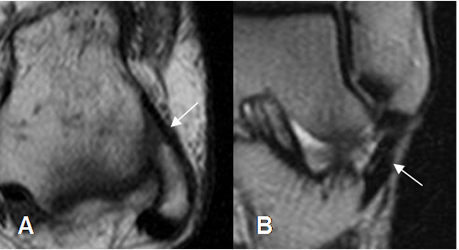

Fig 14. Ligamento tibioastragalino posterior normal.

A: RM axial en T2, B: RM coronal en T2 y C: RM sagital en T1.